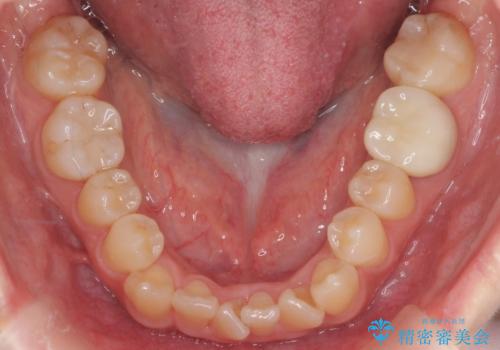

下の前歯のみ1本抜歯しています。

下の前歯の周りの骨は薄いことが多く、無理に並べると唇側の骨がやせて歯ぐきが下がり歯が長く見えます。

それを回避するために今回は下顎前歯を一本抜歯をしています。